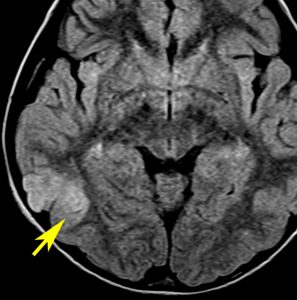

2歳時に偶然発見された,大脳皮質の限局性異形成です。10歳まで症状はでていません。

右側頭葉中側頭回の皮質が厚くなっています。T1強調画像では等信号で見づらいですが,下のフレア画像とT2強調画像では高信号になるのでわかります。

低悪性度グリオーマと間違われることがありますが,大脳皮質だけが異常な信号になっていて,皮質下白質に異常所見がないことが鑑別点です。